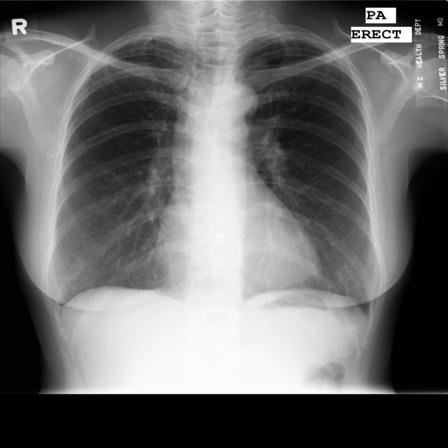

In this section we will show qualitative results of DINOv2 features using principal component analysis (PCA) performed on DINOv2 patch features on X-ray, CT, and MRI scans, following the method delineated in [8]. We will also provide organ segmentation results of linear compared U-Net decoders.

PCA visualization. Figure 2 shows the first three PCA components. The PCA is computed between patches of images that are in the same column, and the first 3 components are shown for X-ray, CT, and MRI scans. Thresholding is used on the first PCA component to remove the background. Just like in natural images [8], the colors of the three PCA components correspond well with the same parts of images in the same category. This is an easier task however, compared to natural images, because there is less variability between examinations on medical images compared to natural images.